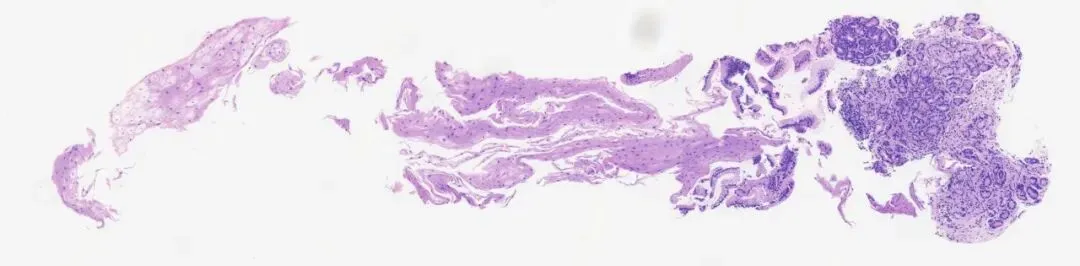

3.典型病理是鳞状上皮局灶性变薄及黏膜固有层显著增生、扩张的贲门腺。